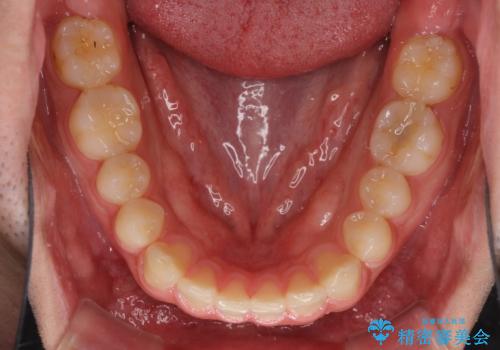

インビザラインによる、すきっ歯の改善

- 前歯がすきっ歯であることを気にして来院された患者様です。

下の前歯がほとんど隠れてしまうくらいの深い咬み合わせであったので、インビザラインを用いて、咬み合わせの高さを改善しながら隙間を閉じていくこととしました。

咬合力で上の前歯が前方に押し出されるようにして隙間ができていましたが、矯正治療により全て閉じることができました。

深い咬み合わせも多少改善され、隙間も閉じたことで、前方に出ていた前歯が引っ込んだため、口も閉じやすくなったとのことでした。